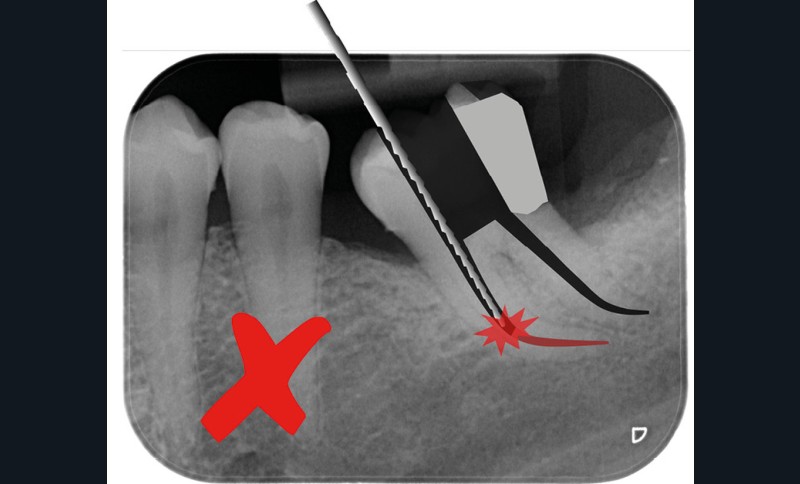

Trop petite

Une cavité d’accès trop petite [2] optimiserait le pronostic biomécanique (préservation dentaire maximale) mais pourrait compromettre le pronostic endodontique : mauvaise lecture de l’anatomie, instrumentation partielle, non ergonomique et avec risque de fracture, défaut de nettoyage des parois canalaires [3], irrigation inadéquate, difficulté d’obturation canalaire, voire d’obturation coronaire. Ce sera le cas des cavités d’accès « Ninja » [4] ou ultraconservatrice (fig. 1), des cavités d’accès « Truss » [5] (fig. 2), des cavités d’accès dites « opportunistes » [6] (fig. 3).